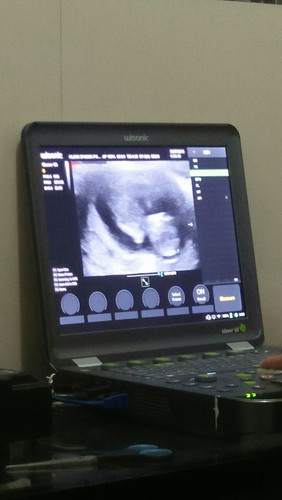

Hasil Usg

Bun saya hamil udh jalan ke 12minggu. Nah karna dapet jam periksa 00.30 jadi rada ngantuk dan gak begitu merhatiin eh pas sampek rumah di cek lagi hasil usg kok dibawah kepala bagian badan kaya ada yg nonjol itu apa ya bun :( semalem gak nanya dan dokter juga ga jelasin cuma bilang semua baik dan normal :(( tp ya jadi kepikiran, doain ya bunda semoga nanti anak lahir normal dan lengkap serta sehaaat..